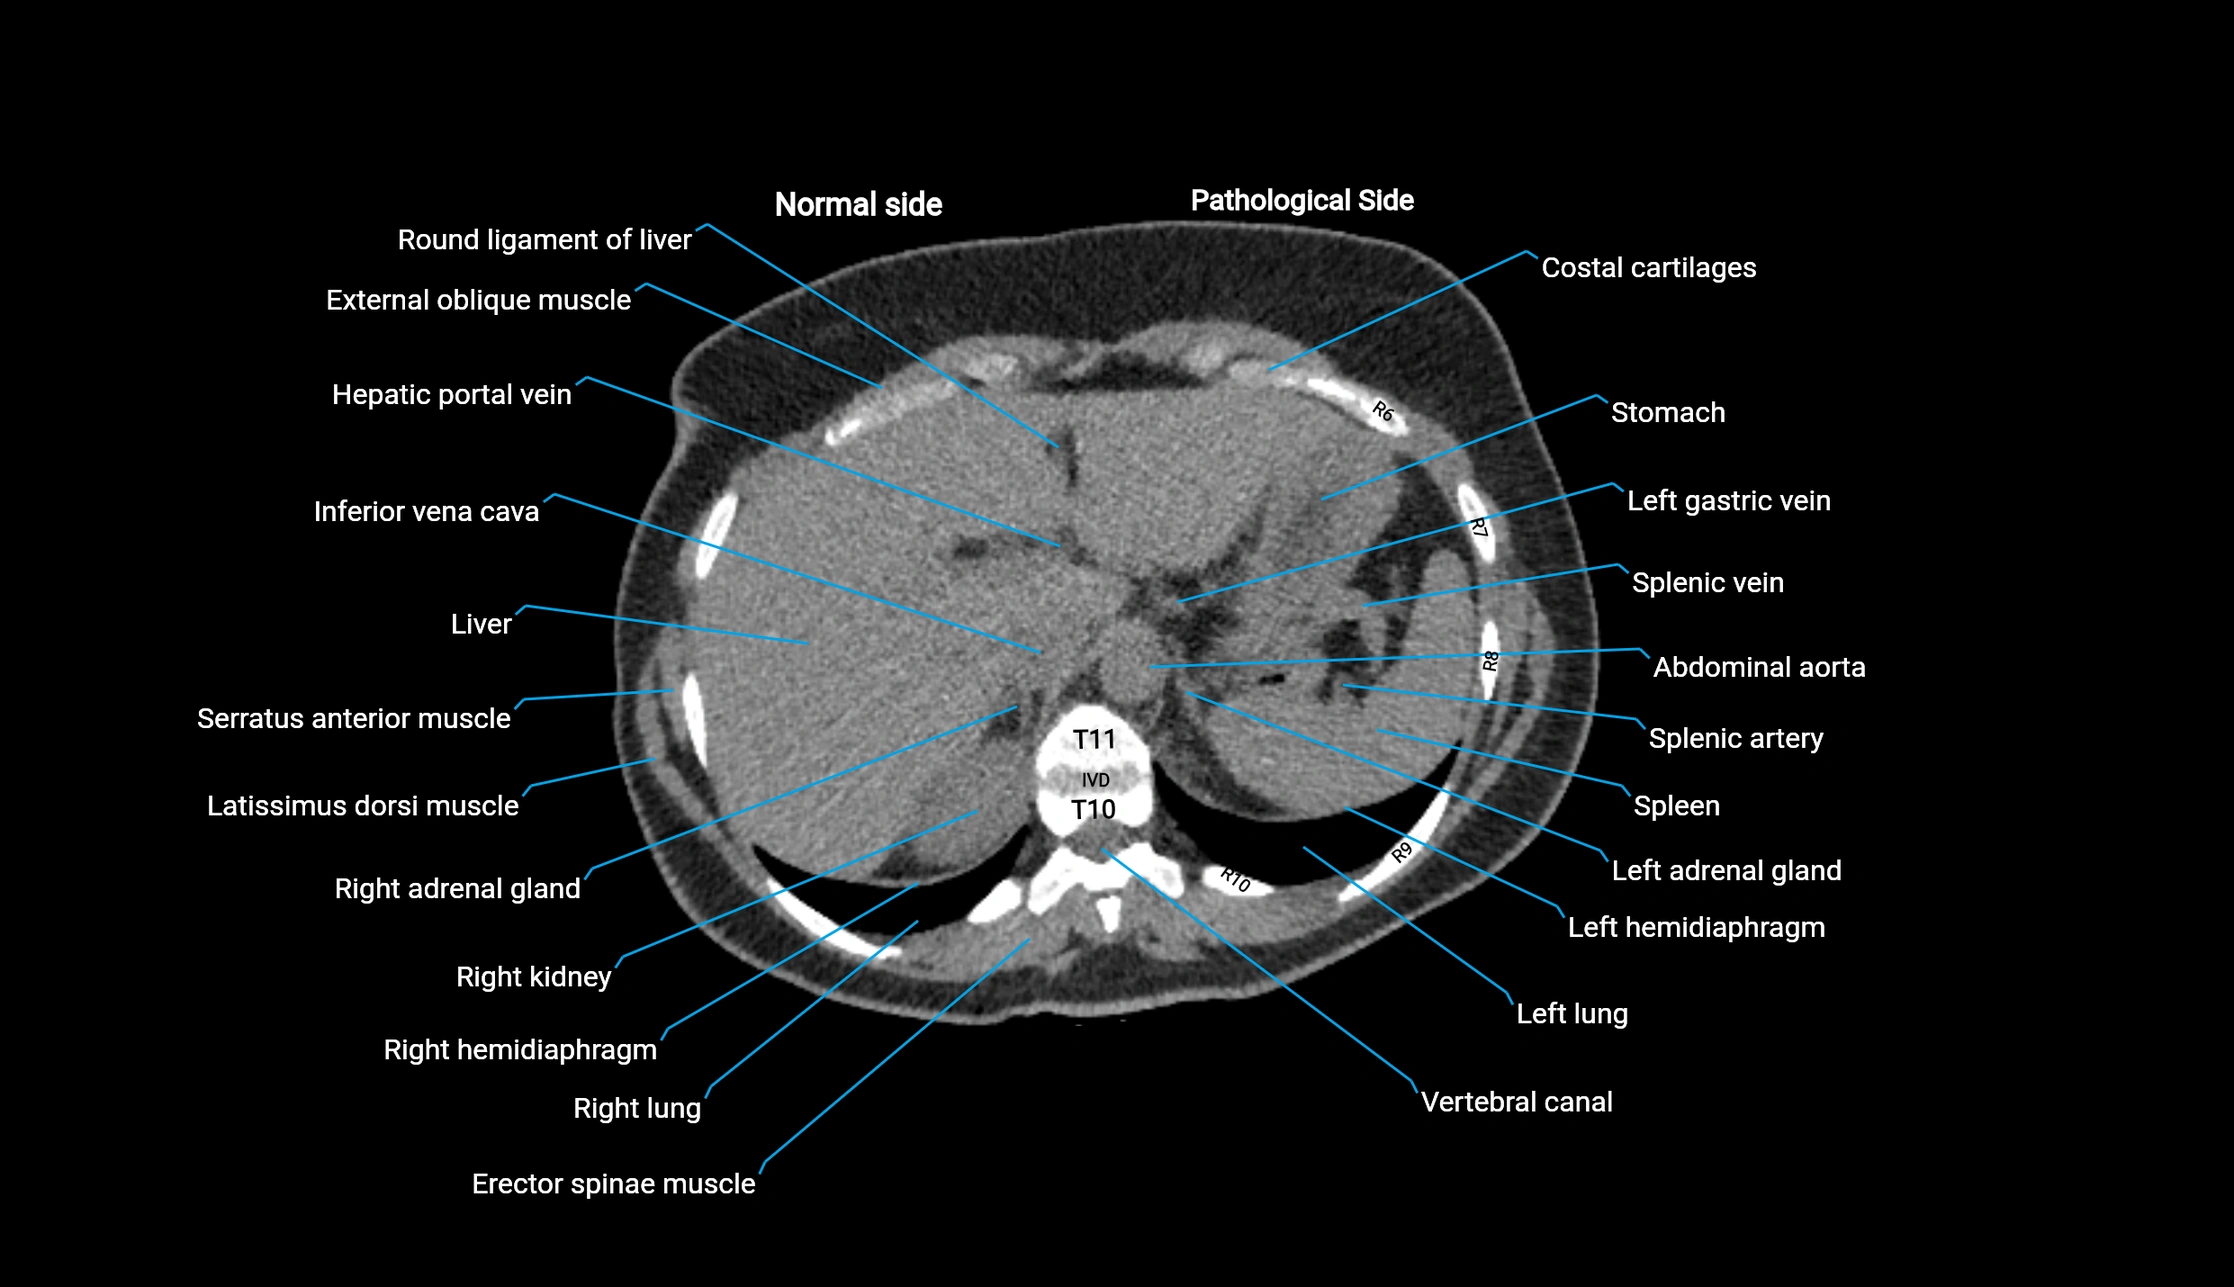

CT image

image